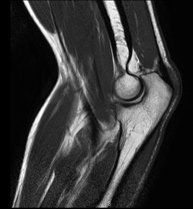

Exploració per estudiar lesions a l'articulació, com trencaments dels meniscals i dels lligaments creuats (únicament es poden detectar amb aquesta prova), condropatia o desgast del cartílag i moltes altres alteracions derivades de l'activitat esportiva i dels canvis degeneratius (osteoartrosi). La durada aproximada és de 18 minuts. No utilitza radiació ionitzant. - RM de Cama